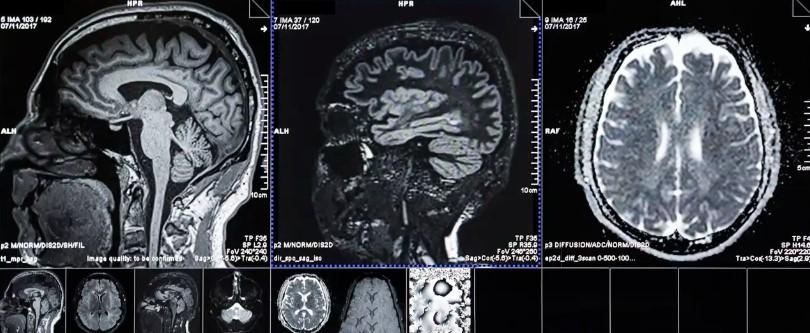

Para visualizar el interior del cráneo se emplean, por lo general, máquinas de resonancia magnética. Estas se basan en el uso de imanes muy potentes y ondas de radio que alteran el estado de los átomos de hidrógeno (u otros, dependiendo de las necesidades de estudio) presentes en nuestras moléculas. Una vez estos átomos vuelven a su estado natural, liberan una energía medible, que se puede detectar y localizar, dando así una visión indirecta de qué sucede en el interior del cerebro. Otras técnicas, como el TAC, emplea rayos X con los que se pueden realizar cortes virtuales de distintas secciones del cerebro.

Gracias a estas tecnologías, es posible detectar desde las áreas cerebrales que se encuentran consumiendo más energía durante una actividad, hasta microrroturas en los vasos sanguíneos cerebrales, además de un gran número de otras patologías. Pero para la Dra. Hilal, también permiten detectar otros parámetros interesantes para su estudio, como la irrigación cerebral o la presencia de traumatismos y la cantidad de muerte neuronal. Así, los investigadores pueden dotar de un valor a la presencia de cualquiera de estas condiciones y establecer un algoritmo que indique la edad del cerebro.